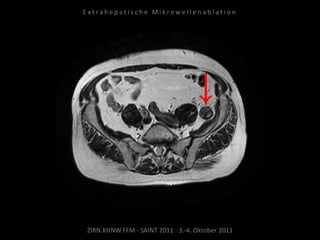

Bildgebung vor MWA:

MRT 03.02.2010

Situation:

Bei Z.n. Prostataresektion + Radiatio

+ Seed nun Rezidiv in kritischer

Position.

Ziel:

Tumordestruktion unter Schonung

der Nachbarstrukturen.

Indikation zur MWA:

Lokal begrenzte Tumor-

manifestation, Position mit MWA-

Sonde erreichbar.

Ablation am 25.03.2010:

1 Nadelposition, 45 W, 7 Min.

Während der Ablation werden

Harnleiter, Harnblase und Rektum

zwecks Hitzeableitung gespült zur

Vermeidung thermischer Schäden.